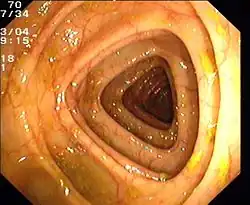

Normaler Dickdarm (Colon transversum)

Normaler Dickdarm (Colon transversum) -